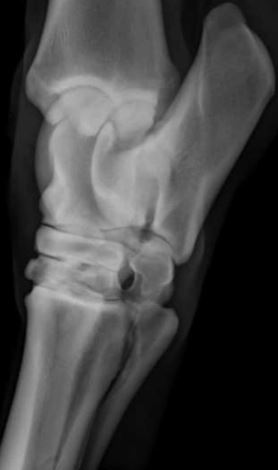

What view is this?

A

DLPMO

Q

DMPLO

On which view can you see both ridges of the talus?

Which aspects are viewed in a DLPMO

Dorso-medial

Lateral-plantar/palmar